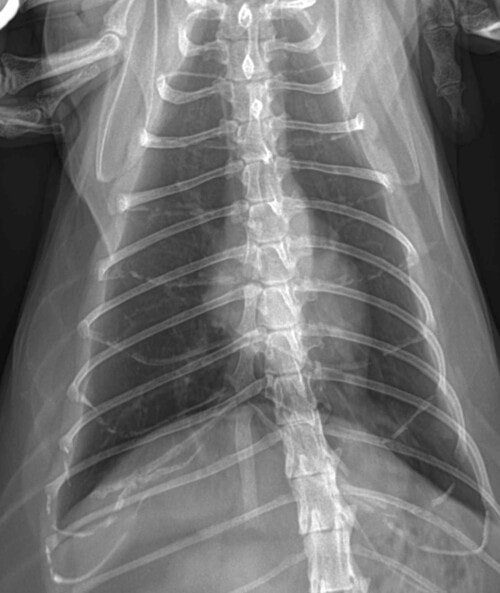

– de ce fait, des radiographies thoraciques sont décidées et ne montrent pas d’anomalie notable.

Photos 4 et 5: Radiographies thoraciques (profil et face dorso-ventrale)

La récupération post-opératoire est bonne et la chatte remarche normalement. Une nouvelle radiographie thoracique au retrait des fils ne met toujours pas en évidence de lésion pulmonaire primitive.

De nouvelles radiographies révèlent alors des lésions ostéolytiques identiques de la dernière phalange de ce doigt III de l’antérieur droit, mais surtout la présence d’une masse tissulaire dans les lobes caudaux, compatible avec une tumeur pulmonaire. Aucun signe respiratoire n’est présent.

Photo 10 : Radiographie thoracique de profil droit.

Présence d’une masse pulmonaire dans les lobes caudaux